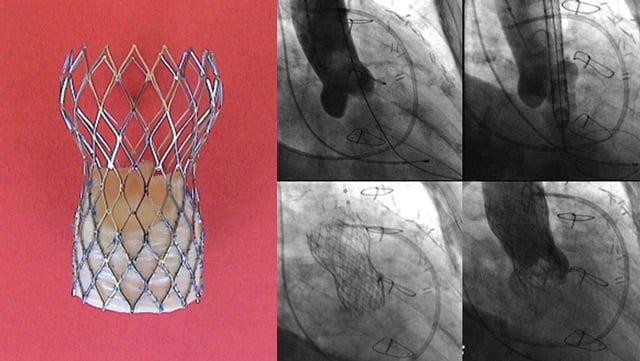

TAVI valve-in-valve - Challenging clinical scenarios

17 Nov 2025 – From PCR London Valves 2025

This session focuses on the complexities of valve-in-valve TAVI procedures, highlighting challenging clinical scenarios such as managing severely regurgitant rapid deployment valves and degenerated stentless bioprostheses. It provides detailed insights into overcoming procedural barriers and strategies for complex valve-in-valve transcatheter aortic valve replacement (TAVR) interventions.

Transcatheter aortic valve implantation (TAVI)

10 Mar 2026

Aortic stenosis (AS) is the most common valvular heart disease leading to intervention. It is characterized by progression from leaflet thickening and calcification to significant haemodynamic stenosis which results in disease-specific symptoms and physical limitations as well as poor prognosis and impaired quality of life if...